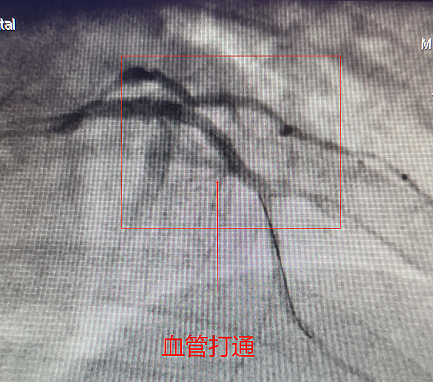

時(shí)間就是生命,患者暫時(shí)脫離了生命危險(xiǎn),但隨時(shí)可能再次發(fā)生心臟驟停,需盡快開通血管,15:22分,在團(tuán)隊(duì)的努力下患者堵塞血管被重新打通,心臟重新恢復(fù)了血液供應(yīng),經(jīng)冠脈內(nèi)溶栓治療后,成功置入心臟支架一枚,造影病變血管通暢后結(jié)束手術(shù)。